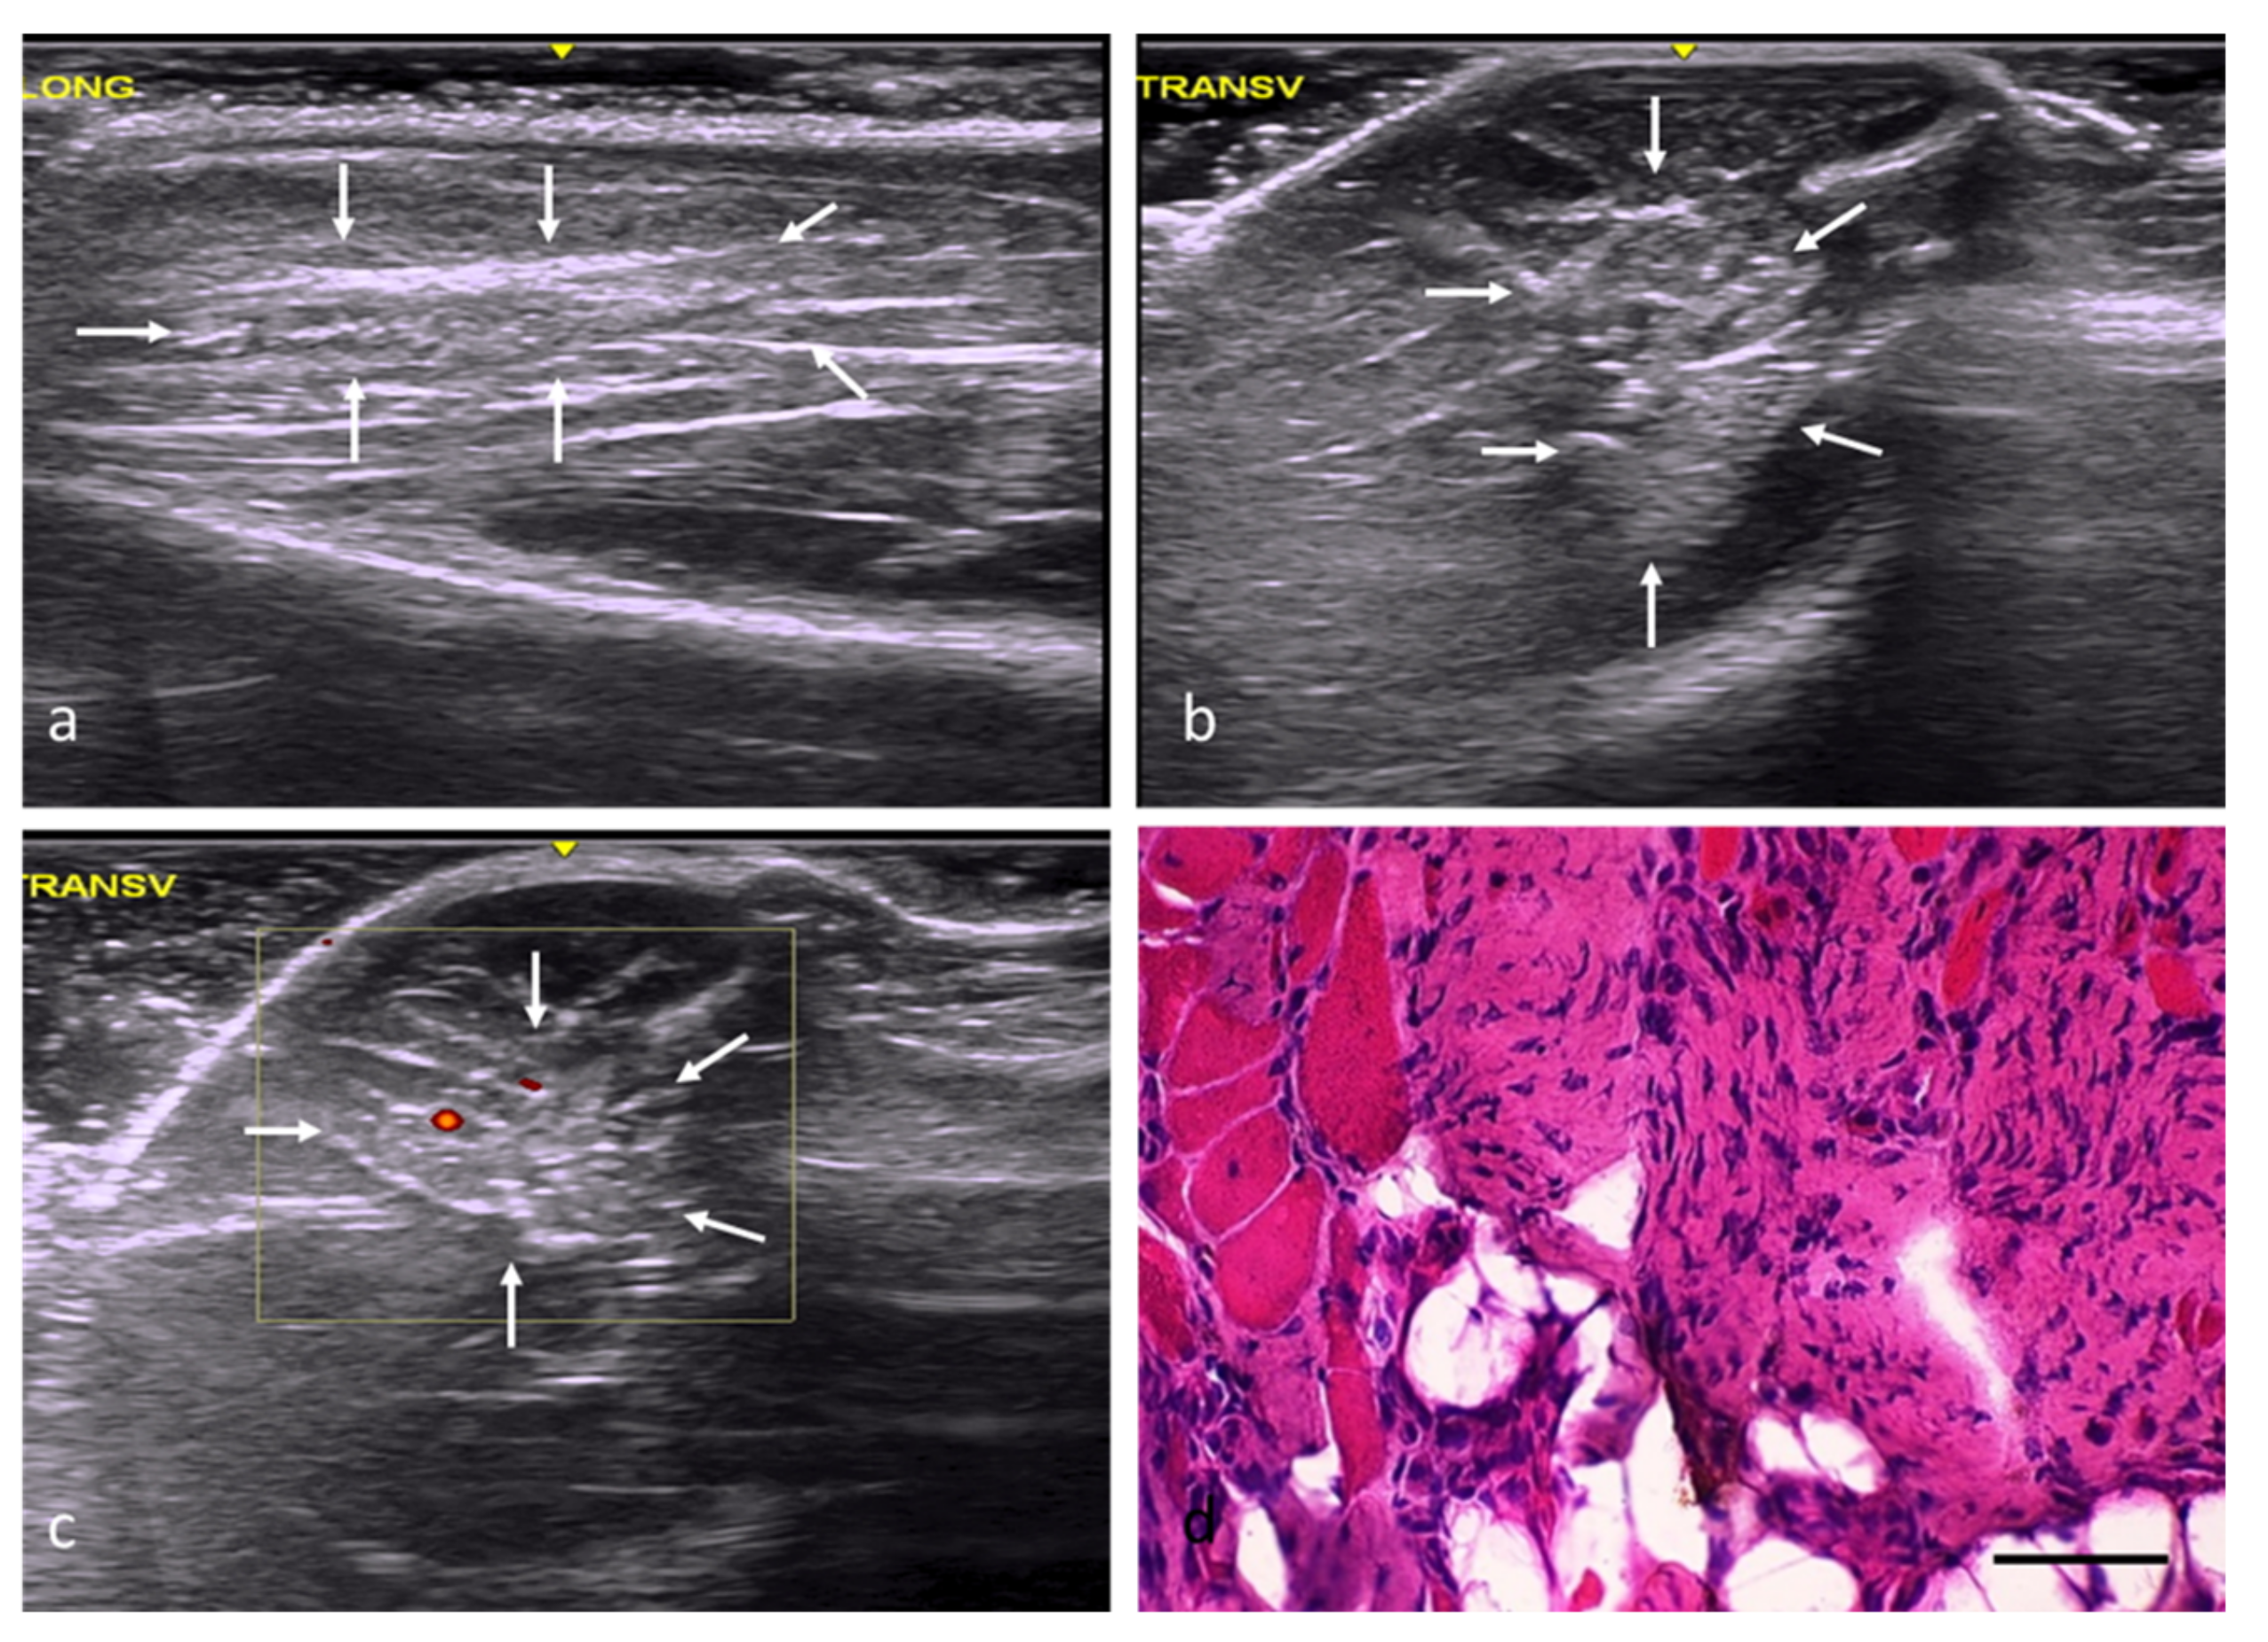

In the adipose tissue (AT) group, the injury margins were slightly unclear, although the implantation areas were hyperechogenic and had a slightly distorted echostructure (Figure 4a–c). According to the histological study, the adipose tissue implanted in the defects had been mostly replaced by skeletal muscle tissue (Figure 4d), with a percentage of fibrosis of approximately 20%. The newly formed muscles exhibited variations in terms of the orientation and size of their fibers, with some being large and others clearly atrophic, but all of them with central or internal nuclei (Table 2).

Figure 4.

AT group. (a) Longitudinal axis, with images of a hyperechoic injury with poorly defined margins, an imprecise morphology, and a slightly distorted echostructure, demarcated by white arrows. (b) Transverse axis, with images of an injury with slightly increased echogenicity, poorly defined margins, and an imprecise morphology. (c) Transverse section assessed by power Doppler imaging, with images of slightly increased intralesional vascularization. (d) Transverse section representative of the muscle histology. H-E. Size scale: 100 µm.